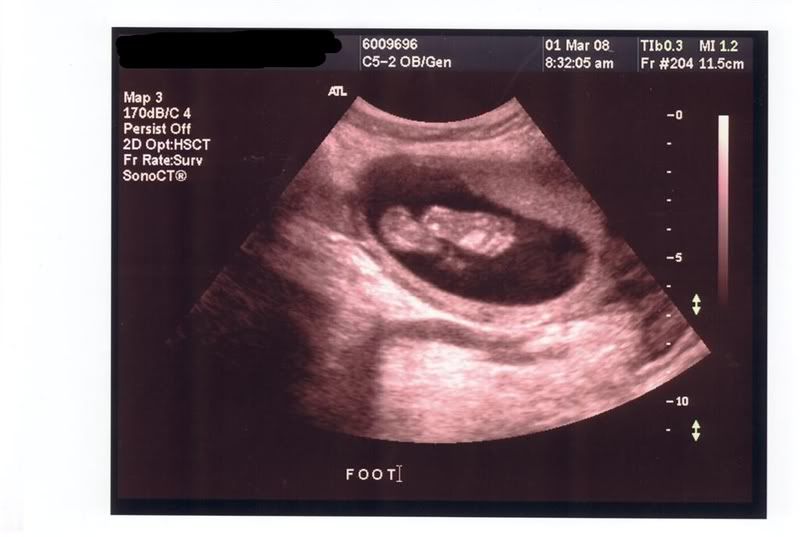

Nevertheless

Here are a couple of pics of my grandson. I don't get to hold him until July, but this early peek is nice!

This one is Mommy on the left and Grampa on the right.

Nevertheless, I think Granpa is gonna pop first!  I like the pic of  the foot. :)